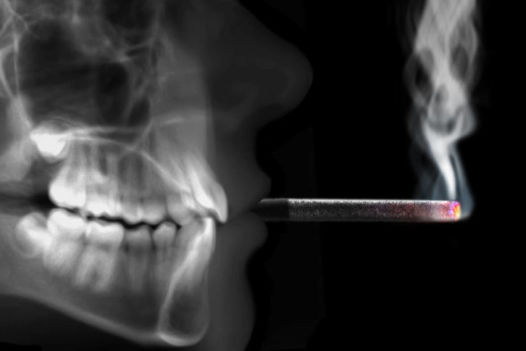

Riesgos del tabaco sobre la salud bucodental

El tabaco es uno de los peores enemigos de la salud bucodental y de la salud en general. Los efectos más visibles del consumo del tabaco en la boca son las tinciones dentales y la halitosis, además, los fumadores también suelen tener alterado el gusto. Pero, aparte de esto, también influye en el desarrollo de otras enfermedades bucodentales.

Como adelantábamos, los fumadores tienen tres veces más riego de desarrollar enfermedades periodontales, que son muy comunes en la población adulta. Los pacientes que no fuman suelen desarrollar inflamación de las encías previamente y tienen también sangrado. Sin embargo, el fumador, por el efecto de la nicotina no suele tener gingivitis, no hay inflamación, sangrado, signos de alerta… Es más difícil que el fumador se dé cuenta por sí mismo.

Además, cabe destacar que las personas que fuman y aspiran mucho el humo o apura mucho los cigarrillos tienen más riesgo de desarrollo de enfermedades bucodentales por el efecto del calor sobre la mucosa bucal, que produce alteraciones.

Por otra parte, el 80 o 90% de los cánceres orales están relacionados con el tabaquismo, hay otros factores de riesgos como el alcoholismo, mala higiene oral…que, si se unen, incrementan el riesgo de padecerlo.